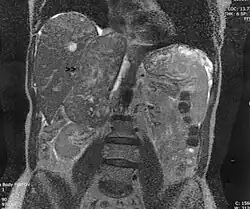

Léiomyosarcome de la veine surrénale droite vue en coupe frontale par IRM

Léiomyosarcome

Les léiomyosarcomes sont des tumeurs musculaires lisses malignes.